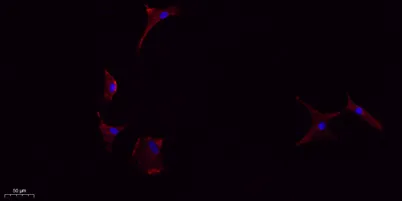

- Validated Applications: WB, IHC, IF, ELISA

- Dilution: Western Blot: 1/500 - 1/2000. IHC-p: 1:100-300 ELISA: 1/20000. IF 1:100-300 Not yet tested in other applications.